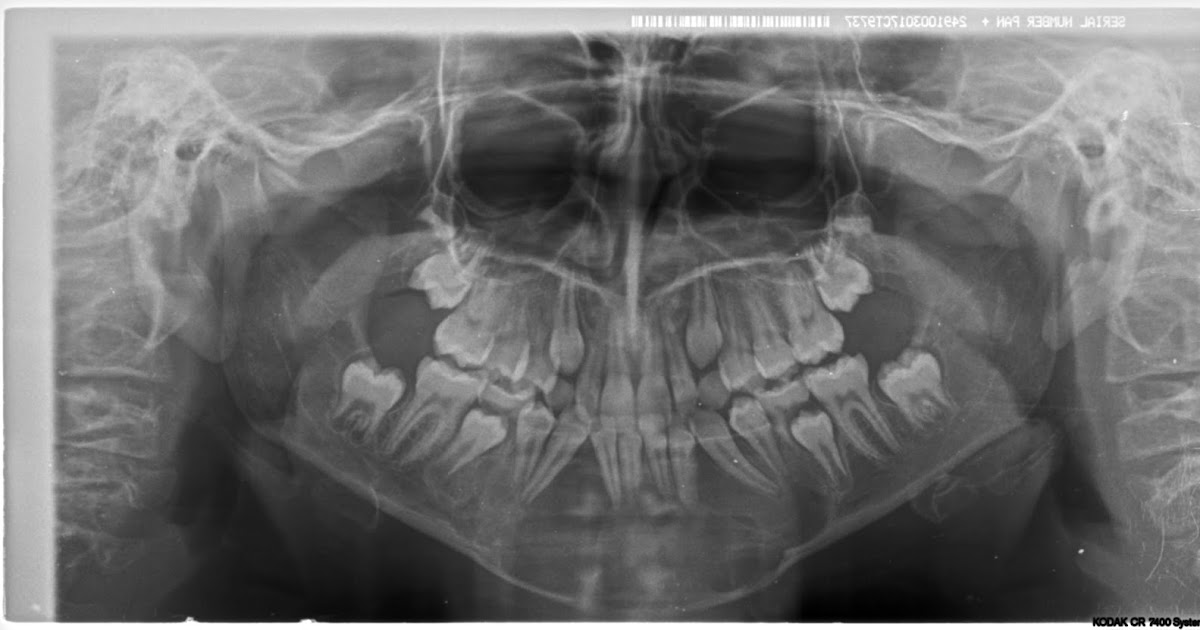

Central Giant Cell Granuloma of the Mandible Requiring Multiple Giant Cell Tumor In Mouth giant cell tumors of the jaw. These tumors often grow near your knee, either. you may have a giant cell tumor at the end of one of your bones. giant cell granulomas are enigmatic lesions of the oral cavity characterised by a peculiar combined proliferation of mononuclear and multinucleated giant cells in a mesenchymal stromal background. . Giant Cell Tumor In Mouth.

Figure 1 from Multiple giant cell tumors in maxilla and skull Giant Cell Tumor In Mouth the distinction between giant cell tumors and giant cell granulomas is challenging, as both entities have overlapping diagnostic criteria, especially in oral. These tumors often grow near your knee, either. giant cell tumors of the jaw. Central and peripheral giant cell granulomas may have similar pathogenesis and histology but differ in their location and biological behaviour. giant. Giant Cell Tumor In Mouth.

Dr. Gabbaypour, DDS, MD Central GiantCell Granuloma Giant Cell Tumor In Mouth giant cell granulomas are enigmatic lesions of the oral cavity characterised by a peculiar combined proliferation of mononuclear and multinucleated giant cells in a mesenchymal stromal background. also called giant cell epulis, giant cell reparative granuloma, osteoclastoma, myeloid epulis. the distinction between giant cell tumors and giant cell granulomas is challenging, as both entities have overlapping diagnostic. Giant Cell Tumor In Mouth.